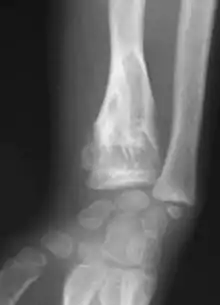

X-ray image showing enchondromas localized in the lower part of the radius of a 7-year-old girl with Ollier disease.

Abnormal bone growth such as shortening or thickening and deformity may be observed in patients of Ollier disease. These bone lesions are visible at birth using radiography but are usually not screened or examined for until clinical manifestations present during early childhood. However, some patients may exhibit no signs of any symptoms.[1] One study found thirteen to be the mean age of diagnosis in patients with Ollier disease. In an X-ray, there would normally be the presence of several homogeneous lesions of an oval or elongated shape with bone edges that are slightly thickened.[3] With age, these lesions may calcify and appear as diffusely minute spots or stippled. Fan-like septations or streaks would be indicative of the presence of several enchondromas. Early detection and consistent and repeated monitoring is important in order to prevent and treat any potential bone neoplasms.

Magnetic resonance imaging (MRI), ultrasound, and scintigraphy are generally not practical for diagnostic purposes. X-rays are not as effective in the monitoring or evaluation of enchondromas due to frequent localized changes also sometimes due to the large number of enchondromas. MRI can sometimes however be used to monitor and evaluate symptomatic lesions in the case of potential malignant transformations.